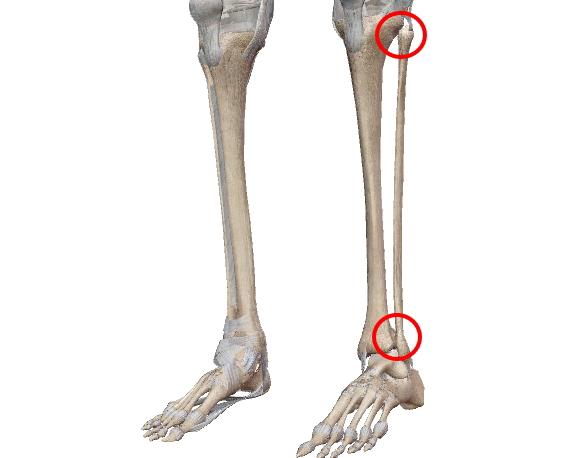

| 軸を保った回旋のみ可能な1軸関節。環軸関節、遠位橈尺関節、近位橈尺関節。 |

| ドアの蝶板(丁番)に似た構造。溝状の凹面を持つ関節窩と円柱状の関節頭からなる1軸の関節。 膝関節、肘関節(椀尺関節)、距腿関節、指節間関節。 *膝関節は屈曲時に回旋できるので顆状関節(浅い球関節)の一面もあります。 |

| 平面に近い関節面が滑るように動く多軸関節。関節面が小さいので可動範囲は極めて小さい。 椎間関節、仙腸関節、肩鎖関節、脛腓関節、手根間関節、足根間関節、豆状骨関節。 *仙腸関節、脛腓関節は、関節面の半分が線維性軟骨結合が占め関節腔が非常に小さいので『半関節』とも。 |